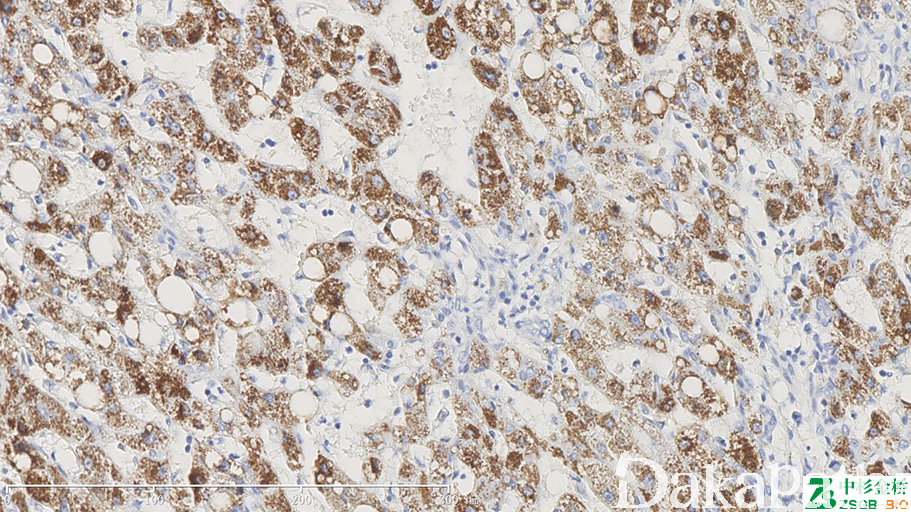

标记正常肝细胞、多数肝癌细胞。HCC 诊断中,HepPar1 是一种具有较高敏感性和特异性的标记物,它的特异性靶点在肝细胞的线粒体,可生产弥漫的颗粒状物质,胞质呈颗粒状。

信号定位: 胞质